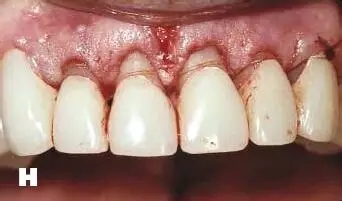

牙周炎發(fā)展到一定階段時(shí),僅采用基礎(chǔ)治療難以取得較好療效,必須通過(guò)適時(shí)而合宜的手術(shù)治療挽救患牙,才能保持牙周組織健康,延長(zhǎng)患牙在口腔內(nèi)的壽命,維持牙列的完整性,促進(jìn)全身健康。其手段包括齦下刮治、根面平整、牙周翻瓣術(shù)、牙齦切除術(shù)、牙周夾板固定術(shù)等。

1、美容手術(shù):針對(duì)牙齦增生、影響美觀效果的患者,進(jìn)行牙齦的美容切除手術(shù),修整牙齦的形態(tài),恢復(fù)美容效果。